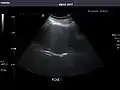

Right kidney

Kidneys: Right and left kidneys measure 11.5 cm and 12 cm in length respectively. No hydronephrosis. Small left lower pole kidney cyst.